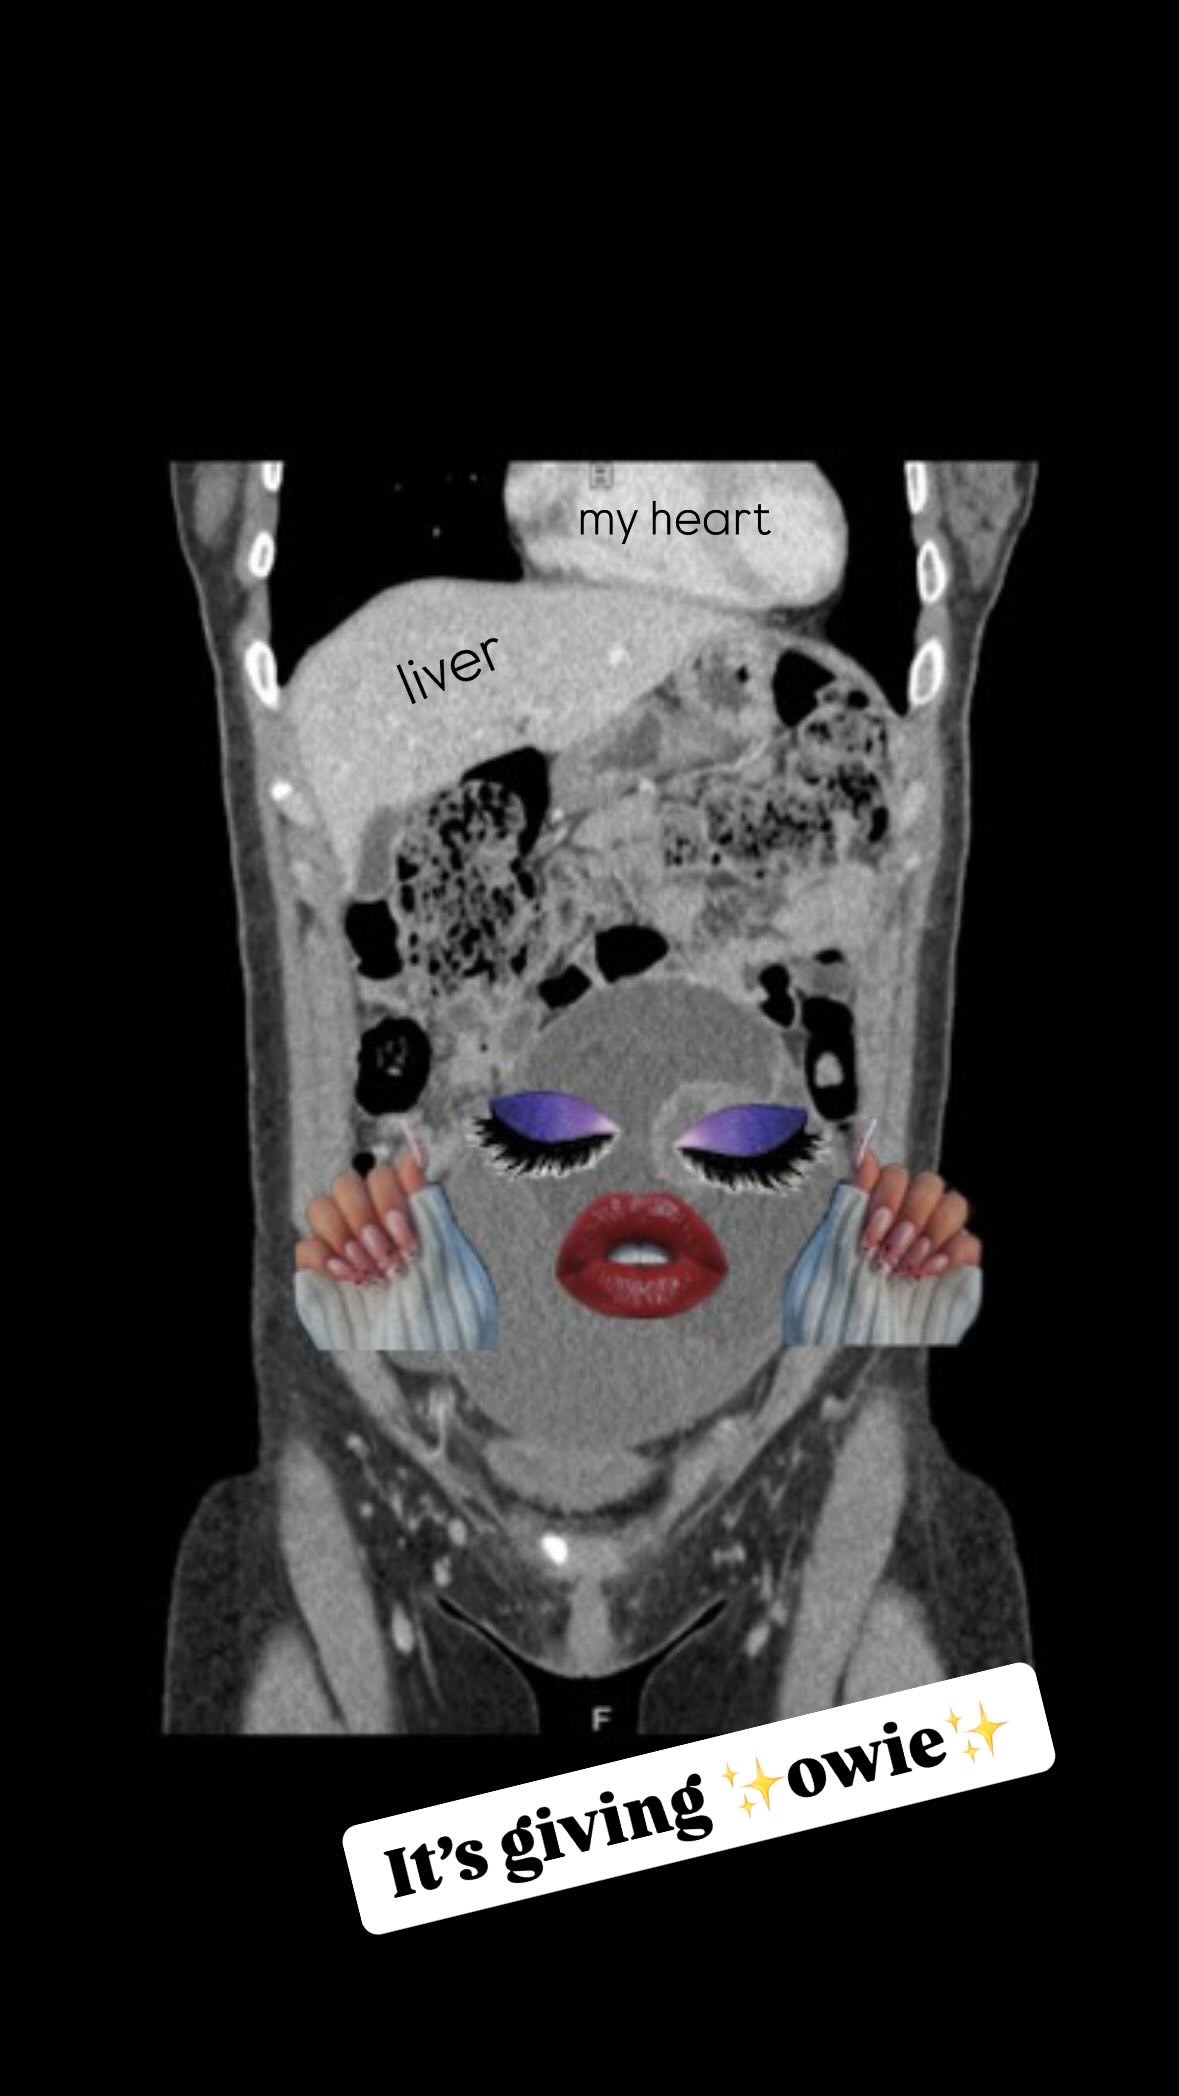

Turns out this large lump in my gut is a Complex Ovarian Cyst measuring a whopping 16.5 cm in diameter and ~1,000 ml in volume! That's bigger than a grapefruit and is painfully squishing all my other organs and nerves.

After ultrasounds, CT scans and a few doctor exams, it has been confirmed that surgery is needed to remove the mass (whose legal name is Francyst O. Varian).